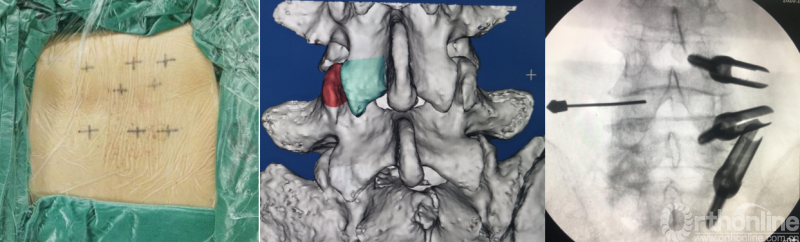

BELIF技术十步法

详细步骤:一定、二剥、三凿、四分、五咬、六切、七牵、八铰、九填、十置

第一步“定”:X线定位在上位椎体下关节突下三分之一部;

第二步“剥”:剥离器+射频剥离、止血、造腔,显露下关节突尖部;

第三步“凿”:凿除部分下关节突;

第四步“分”:分离上关节突及黄韧带;

第五步“咬”:咬除部分上关节突,显露椎间盘及神经根;

第六步“切”:切除椎间盘;

第七步“牵”:神经拉钩牵拉保护神经根;

第八步“铰”:铰刀置入处理上下终板(刮勺置入处理终板);

第九步“填”:椎间隙填塞植骨;

第十步“置”:置入融合器、经皮钉。